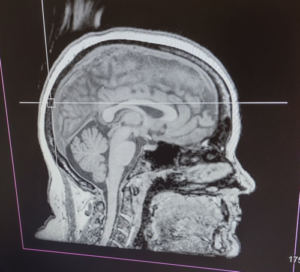

They gave me ear plugs and also put these giant foam blocks on either side of my head (mainly to keep me from moving my head) that really insulated me from the sound. With all that insulation, I actually felt it wasn’t any more noisy than being underwater at the swimming pool. Everything had that kind of far away, dull echo sound quality to it. My head and the blocks were strapped down into place and away I went into the MRI so they could take 1 millimeter pictures of my brain from the front to back, side to side and top to bottom. I was in there for about an hour and did my best to meditate. They frequently checked in to make sure I was doing ok and gave me updates on how long each “next segment” would take. Not like it meant anything. When you’re trapped in a tube with nothing but your thoughts, time becomes a bit meaningless.

All this technology helped to map out where my head was in the physical space in front of the camera. The camera is a dual lens device that has a long neck and if you can remember the character "WALL-e" from the movie, you'll have kind of an idea what that looks like. All these traced marks were overlaid on top of the MRI images they had loaded into the computer and helped them to aim the magnetic field to the very precise spot in my brain called the dorsal lateral prefrontal cortex. (Image 1 above.)